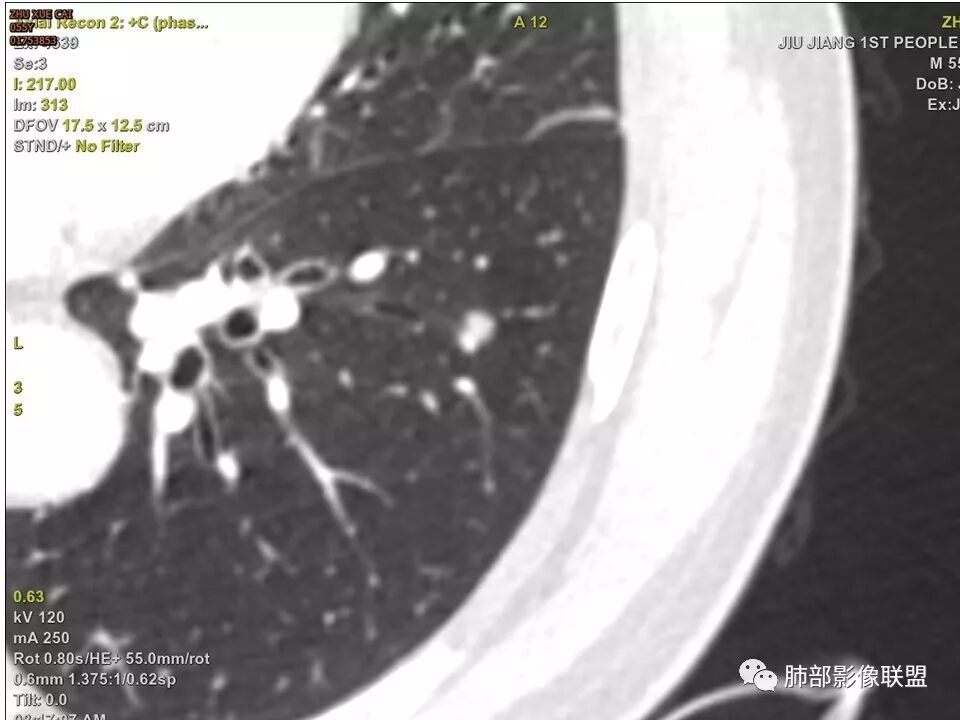

边缘有光滑,有圈黑晕,强化弱,似乎有脂肪密度,支气管截断的部位很自然,没有鼠尾状狭窄,考虑软骨型错构瘤?

这个支气管开口位置,如果是肿瘤应该有管壁浸润,也应该有膨胀感,这个没有,不像恶性肿瘤的支气管截断

病灶部分平直丶内收,有脂肪密度,不强化支持错构瘤。部分病灶有结节堆积感,分叶,与支气管、肺动脉关系密切,需鉴别腺癌。不强化进一步结核结节。

这个病例要特别关注增强前后ct值

晨读病例,强化值小于20,还是提示良性,感觉支气管截断是坑,所以考虑错构瘤?肺癌待排

边缘平直,主要强化值小于20,说明基本不强化,提示良性

不是假象,是真的堵了,我工作站薄层做了气管曲面重建,仿真内窥镜也显示堵了

也咨询了病理科老师,肺软骨瘤来源于支气管透明软骨,理论上可以从黏膜下,突向支气管腔内生长,对支气管造成压迫性的阻塞。影像上和软骨瘤样错构瘤没法区分

典型CT特征包括:(1)圆形或椭圆形边界清楚的病灶。(2)大小1~4cm,有轻微分叶改变。(3)较均匀的软组织影,多伴有钙化。(4)无毛刺,卫星灶及肺门或纵隔淋巴结肿大。(5)CT增强扫描无强化或轻度强化,其强化可能与软骨瘤间质中的薄壁血管或周围慢性炎症反应有关。